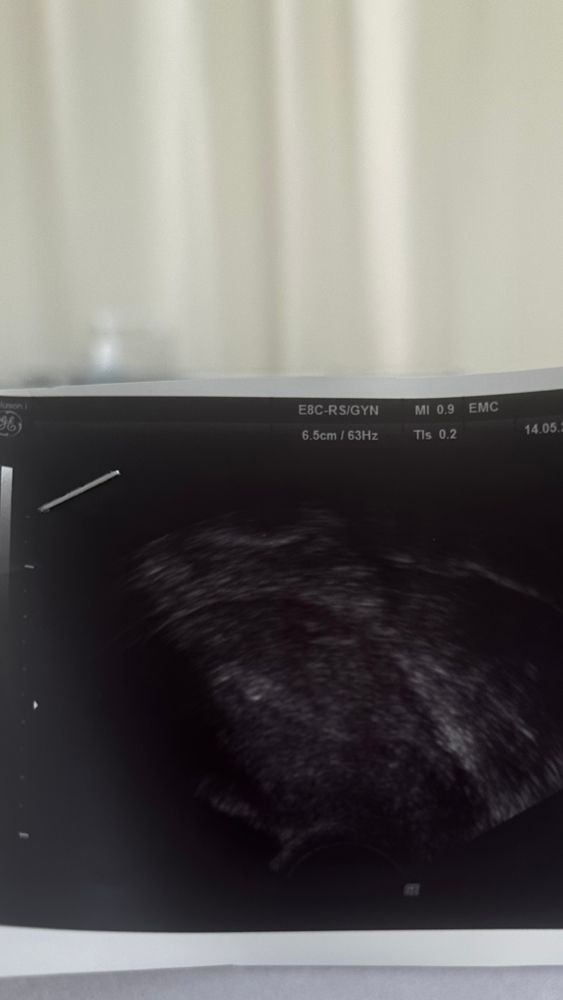

Самочувствие после переносаНу что же. Маленькая светящаяся точечка на узи, уже со мной. Давно забытое чувство, волнение, пульс зашкаливал) скоро врач принесет рекомендации, к утрожестану 600 добавят пролютекс точно укол в день.

эндометрий был 11.5, у меня с сыном при переносе был такой же.